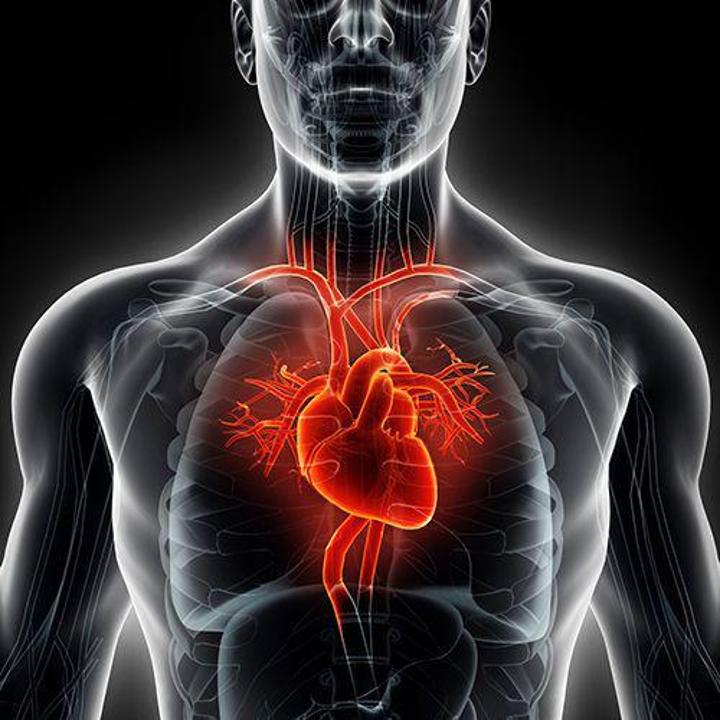

أفريقيا برس – الجزائر. اكتشف علماء جامعة بريستول البريطانية طريقة لإصلاح الأوعية الدموية التي تغذي القلب، المتضررة بسبب قصور القلب.

ويشير الموقع الرسمي للجامعة البريطانية، إلى أنه لفهم كيف يحصل تلف القلب، أجرى الباحثون دراسات على فئران مخبرية مصابة بمرض السكري بنوعيه الأول والثاني، تضمنت دراسة الكأس السكري أو الكنان السكري (Glycocalyx) وهي طبقة هلامية القوام في الأوعية الدموية.

اتضح أنها موجودة في الأوعية الدموية الصغيرة للقلب، تتضرر بشكل أساسي نتيجة أمراض مختلفة.

ووفقا للباحثين يحصل هذا التلف نتيجة حركة السوائل في جدران القلب، ما يؤدي إلى ظهور الوذمة وتصلب عضلة القلب، وبالتالي تمنع القلب من الاسترخاء بين الضربات وضخ الدم إلى الجسم.